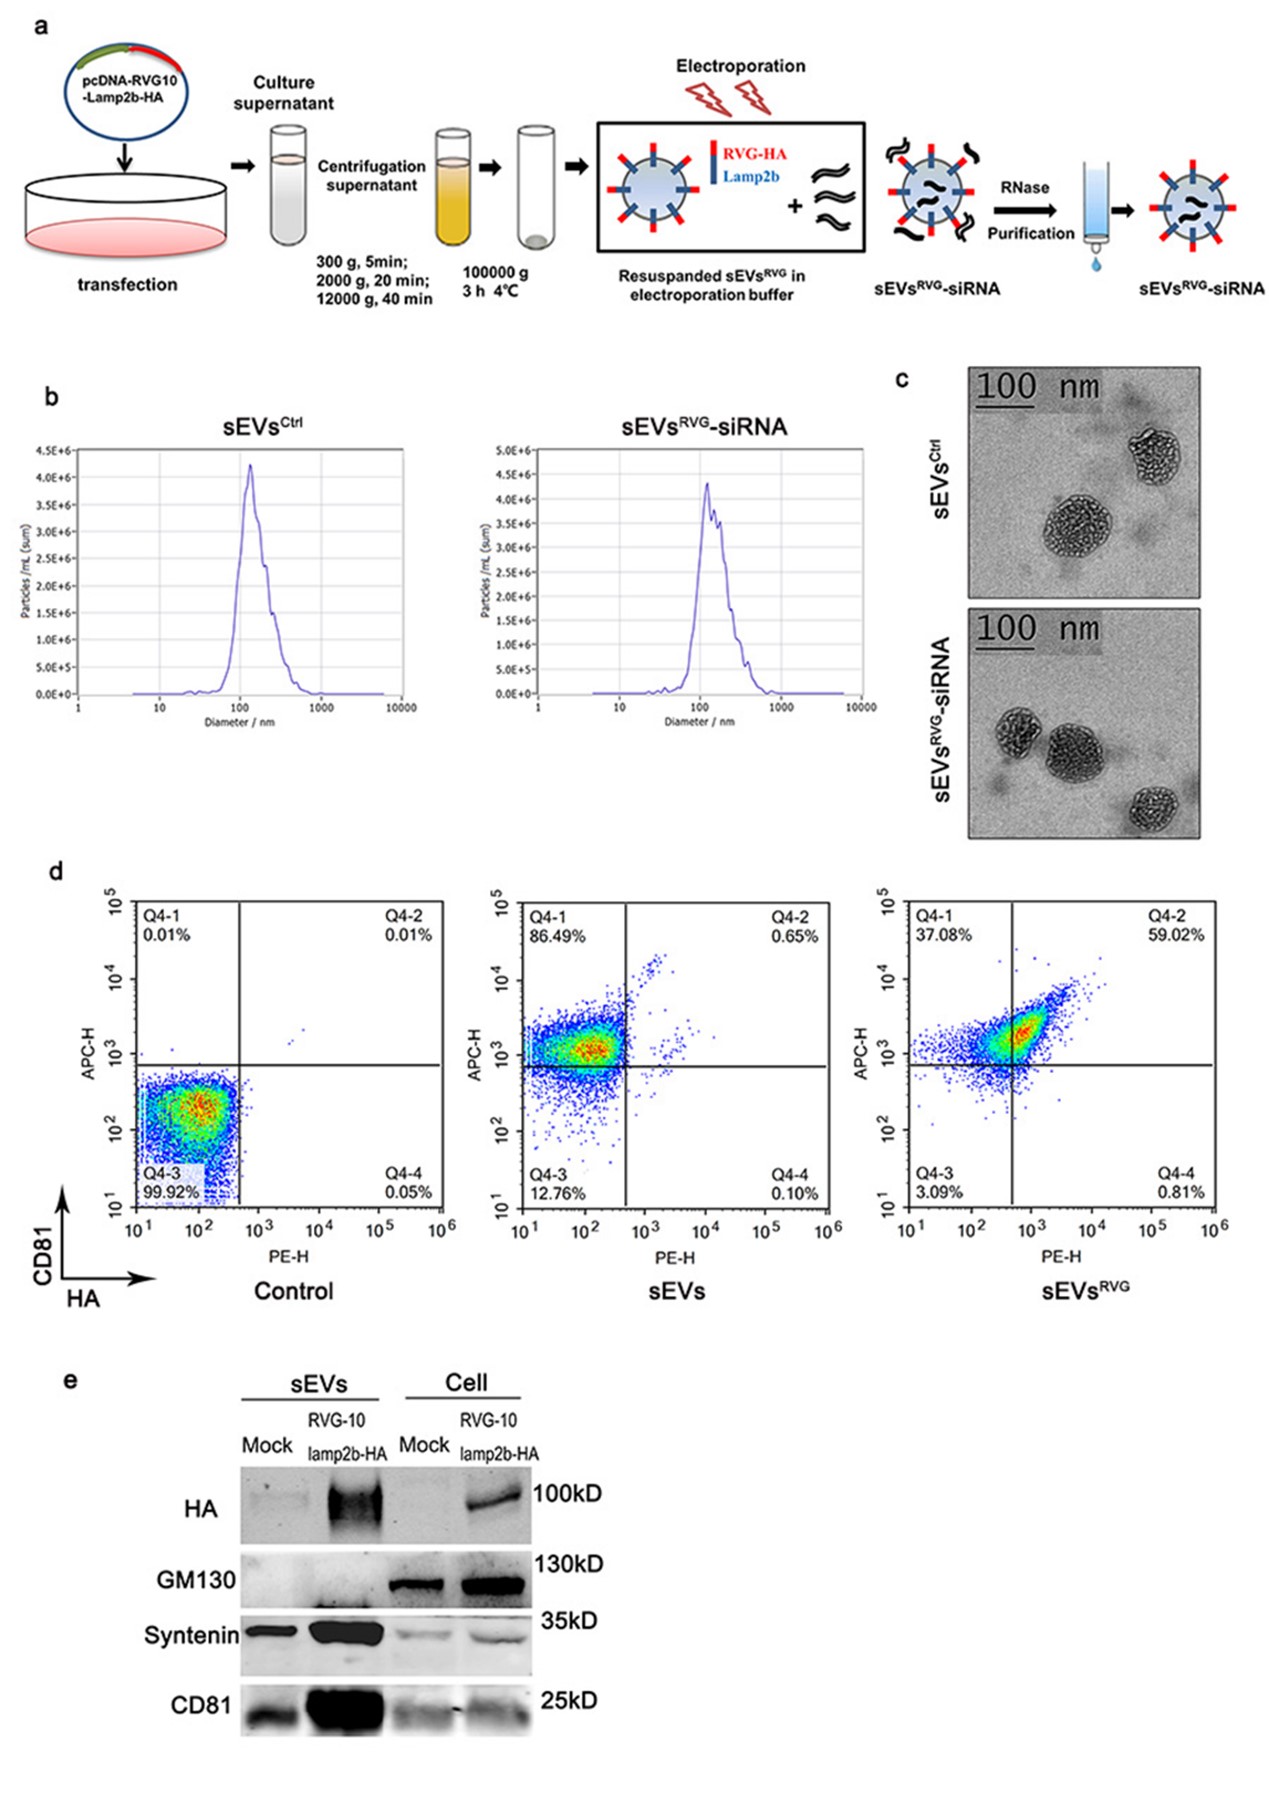

图2:sEVsRVG-siRNA 的制备和表征

为了开发一种能够穿越胎盘和血脑屏障的特异性抗病毒疗法来治疗ZIKV引起的小头症,我们设计了靶向脑部神经的细胞外小囊泡(sEVsRVG)并装载抗病毒siRNA(ZIKV特异性siRNA)来抑制ZIKV。细胞外小囊泡(sEVsRVG)的脑部神经特异性靶向是通过将sEVs膜蛋白lamp2b和神经靶向性的狂犬病毒糖蛋白衍生肽(RVG)融合递呈在细胞外囊泡上,在细胞及动物水平验证了sEVsRVG-siRNA的抗病毒能力